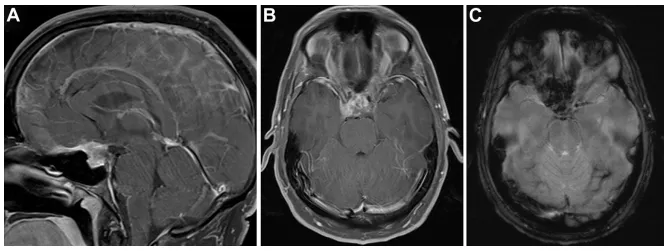

然而一年零一个月后,熟悉的剧烈头痛再次袭来,这次还伴随着双眼发黑,持续了约半小时。增强MRI检查发现肿瘤又出现了,而且与垂体腺分界不清,再次沿着蝶骨平台和斜坡颅侧生长。新出现的强化信号提示肿瘤性质可能发生了变化(图2)。眼科检查这次发现了右眼中心暗点和红色色觉异常。

图2.(A、B)矢状位及轴位T1加权增强MRI显示鞍区及鞍上占位复发,与垂体腺分界不清,病灶再次沿蝶骨平台及斜坡颅侧延伸。(C)梯度回波序列显示病灶呈显着磁敏感效应,并新出现强化灶。